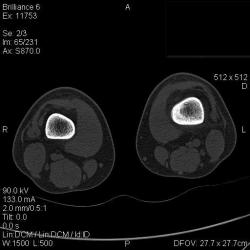

Да, на мой взгляд, состояние после обычного "травматического перелома" (трещина), не думаю, что имел место "патологический перелом", так как костная ткань "патологически изменена" минимально. "Перистальная реакция"локальная тоже есть, на КТ "локальная  зона склероза" - все это свидетельствует именно об этом. Хотя в памяти у меня хорошо отложился Ваш последний случай о локальном утолщении кортикального слоя, когда "яйца в гнезде" еще не было. То, что анамнестически "травмы не было" - ничего не значит. Вы, по всей видимости, тоже часто встречались с такими случаями, когда ребенок не акцентировал внимание на "травме", как таковой, хотя клиника есть, боль есть. Конечно, рентгенограммы - не дай бог - ни скиалогии, ни структуры.

Локальный гиперостоз, выраженный болевой синдром, структура губчатого вещества диафиза не изменена наводит только на остеойд-остеому.

Согласна с Ola-la - рентгенологическая картина более всего соответствует стрессорному перелому, хотя для него характерна локализация в б/берцовой кости. Меня однако, смущает и настораживает клиника - это как раз тот случай, когда я бы не дала 100% гарантии, что так не может манифестировать остеосаркома... Поскольку другие методы (МРТ, сцинтиграфия) вряд ли помогут, я бы взяла пациента на короткое ( 2недели - месяц) динамическое наблюдение.

Буквально заключение гистологов передать не могу (мой недочет, нужно было сразу выложить на сайтОй-ой-ой), но приблизительно помню - данных за специфический процесс нет, картина консолидирующегося перелома.

Так что, по всей видимости, это действительно был стресс-перелом. Который крайне редко встречается. Хоть статейку в журнал пишиУлыбаюсь.